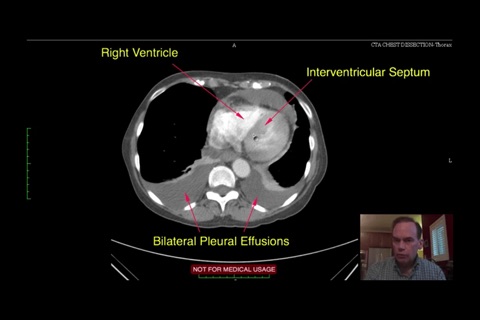

随着科技日新月异,新型医疗仪器不断推陈出新,让医疗专业人员在疾病诊断上,提供极大的帮助。除往日的X光,计算机X射线断层造影术(Computed Tomography, CT),B超(Ultrasound)外,新型的工具包括磁共振显像(MRI),核医学(Nuclear Medicine, NM),如正电子发射断层照相术(Positron Emission Tomography, PET),单光子发射体层摄影术(Single-Photon Emission Tomography, SPET) 等等。新型的工具能减少对病人的伤害和提供不同方面的诊断资讯。

有见及此,我们制作了本程式,以来自海外的英语放射诊断科视频, 提供各种诊断个案,并加以评述,望能帮助医生,作出更符合临床表现的诊断,是医生和医学院校的学生学习影像诊断入门的必备软件。